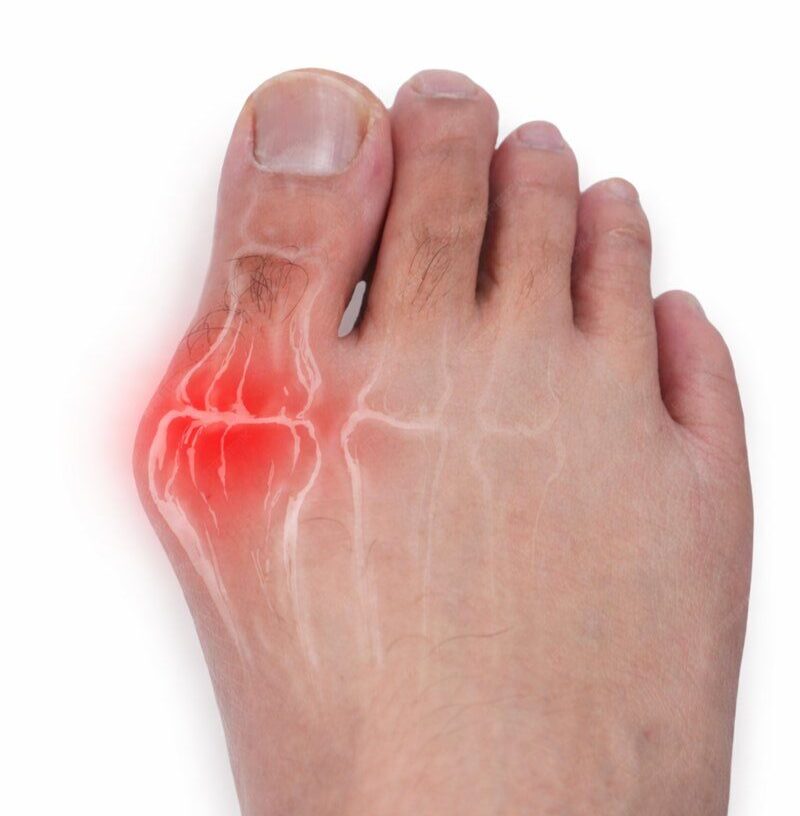

"Operar os dois pés e pisar imediatamente!” esse lema gerou resultados incríveis no tratamento do pé plano e do joanete. Conheça as técnicas que foram apresentadas pelo Dr Rodrigo Astolfi na Itália (pé plano) e na Coréia do Sul (joanete).